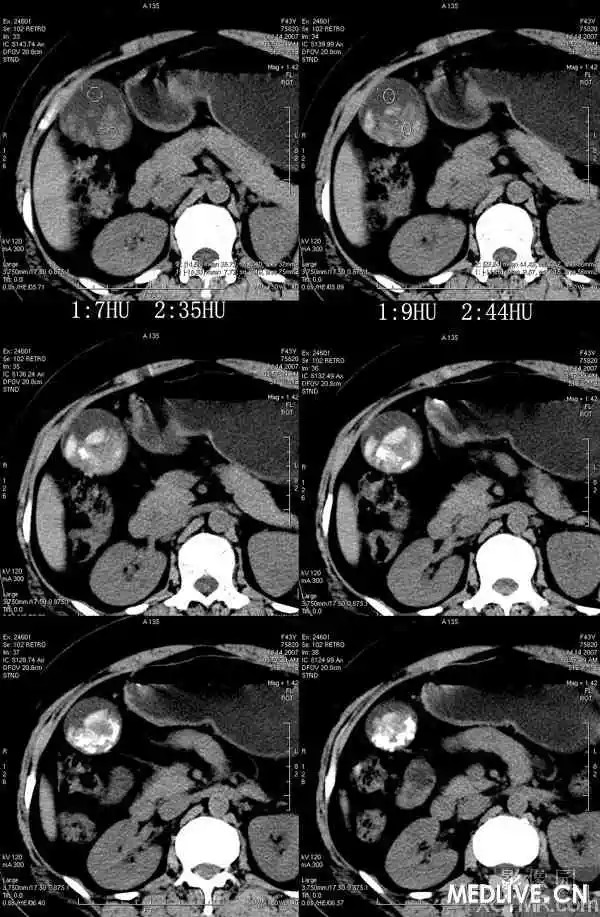

【影像表现】

胆囊内混杂高密度影,内有不规则形钙化,胆囊壁略增厚。

CT表现因结石化学成分不同,可为高密度、等密度、低密度、环状结石。等、低密度结石CT不易发现,胆影葡胺增强检查见胆囊内可移动的充盈缺损可明确。